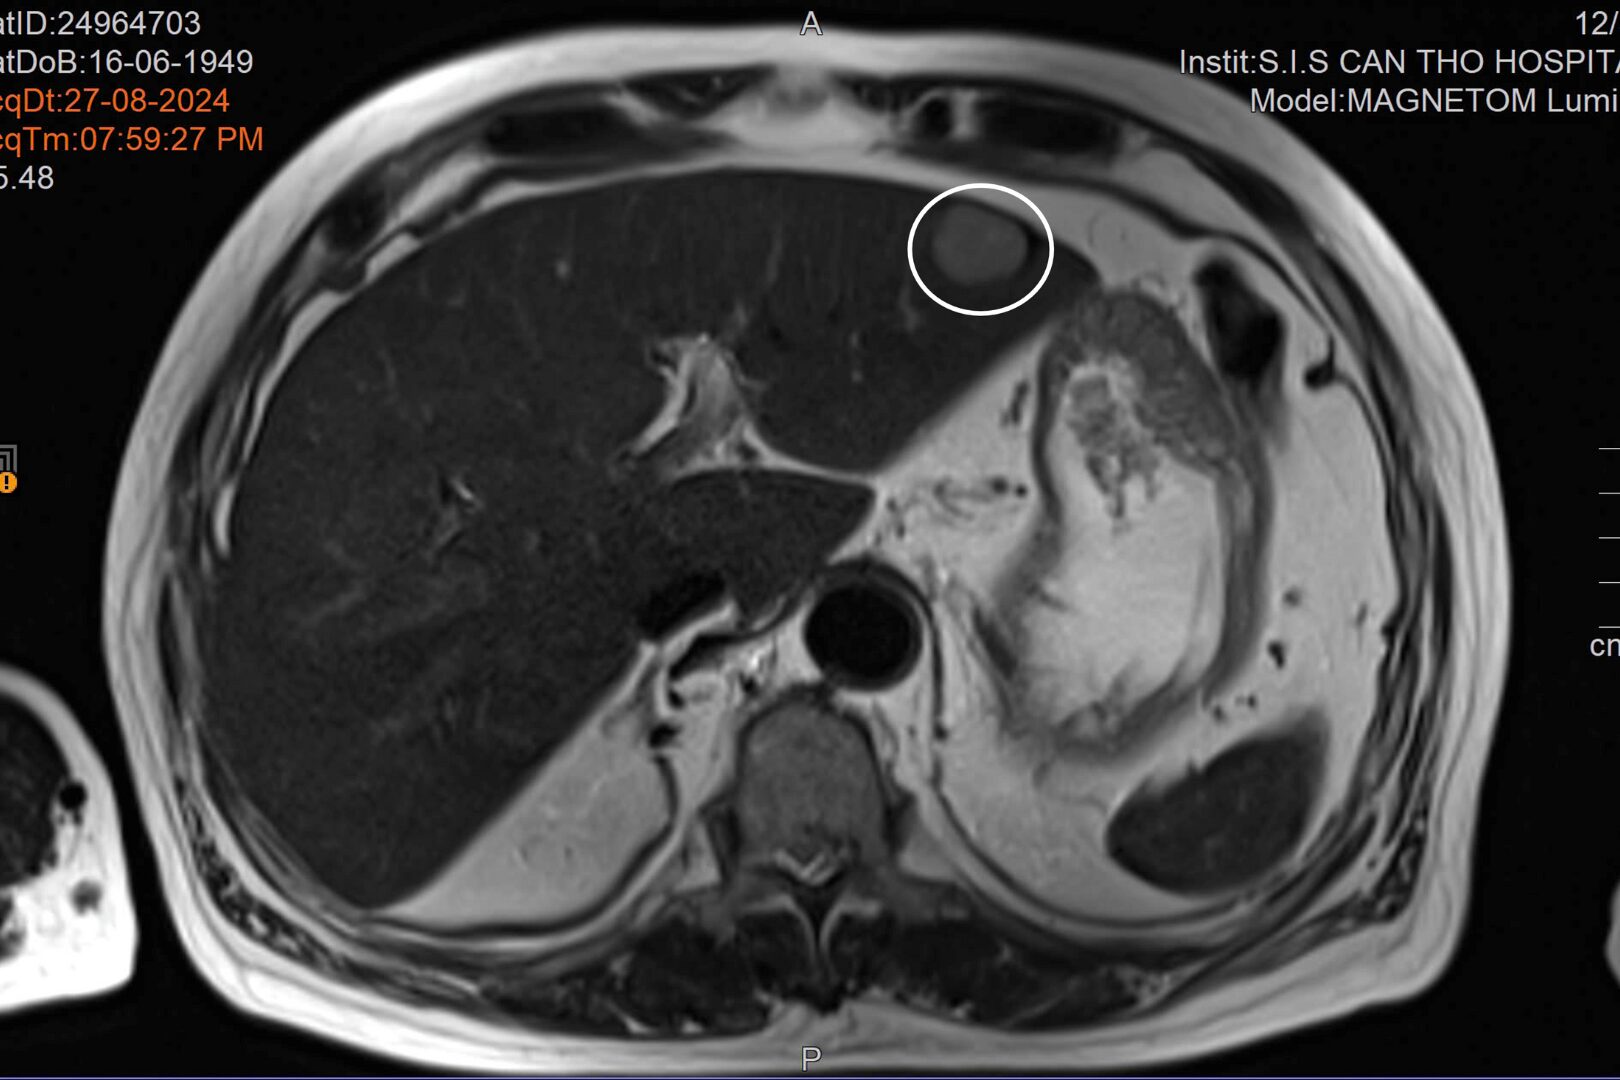

U gan (ảnh trên) và u túi mật được phát hiện khi bệnh nhân đến tái khám tình trạng tai biến (Ảnh: BVCC)

Trong đợt tái khám, kết quả các cận lâm sàng cho thấy bệnh nhân có những tổn thương ở gan và túi mật. ThS.BS Đặng Văn Sô Đa – Khoa Ngoại tổng tợp, Bệnh viện Đa khoa Quốc tế S.I.S Cần Thơ cho biết: “Ung thư túi mật là một bệnh lý hiếm gặp. Bệnh nhân lại cùng lúc có ung thư túi mật và ung thư gan. Bệnh nhân được điều trị bằng phương pháp nội soi ổ bụng, cắt túi mật nội soi và cắt một phần gan trước khối u”.